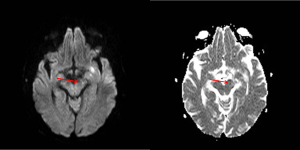

Se observa una lesión isquémica con una degeneración walleriana secundaria que también se observa en las secuencias de difusión y en el mapa ADC:

De una forma sencilla, la evolución de las alteraciones en la señal de la resonancia cerebral a lo largo del tracto de sustancia blanca refleja los cambios bioquímicos que ocurren durante la DW. Las alteraciones en la difusión que se muestra hiperintenso y la hipointensidad de señal en el mapa ADC sí que se han descrito en la fase aguda en la primera semana distal a una lesión por encima y son indicativas de degeneración walleriana. Serían los cambios más precoces detectables. Las alteraciones de la DW de las secuencias T2 suelen aparecer en la 3-4 semana aunque hay casos muy precoces que aparecen en las 2ª semana. Este caso es particular por el hecho que aparece precozmente.

Es importante revisar las imágenes y detectar los cambios precoces en las secuencias de difusión y mapa ADC distal a una lesión isquémica por las implicación pronóstica de las mismas.